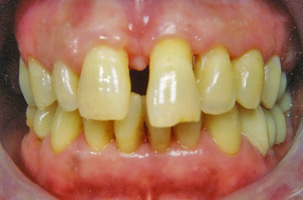

Η περιοδοντική νόσος μετακινεί τα δόντια καθώς το κόκαλο που τα υποστηρίζει υποχωρεί σταδιακά. Έτσι τα δόντια εμφανίζουν διαστήματα μεταξύ τους ή/και περιστρέφονται. Η ορθοδοντική θεραπεία επαναφέρει τα δόντια στις ορθές τους θέσεις και τέλος τα ακινητοποιεί ώστε να διασφαλιστεί η μακροβιότητά τους στο στόμα.

Προβλήματα λόγω της κακής θέσης των γνάθων μεταξύ τους μπορούν με την κατάλληλη ορθοδοντική μετακίνηση των δοντιών να καμουφλαριστούν και να επιτευχτεί μια αποδεκτή σύγκλειση παρά την υπάρχουσα σκελετική ανωμαλία. Παρόλα αυτά, όταν οι διαφορές μεγέθους ή/και οι σχετικές σχέσεις των γνάθων μεταξύ τους είναι έντονες, δεν είναι δυνατή η διόρθωση αποκλειστικά με την ορθοδοντική θεραπεία. Σ’ αυτες τις περιπτώσεις η ορθογναθική χειρουργική είναι απαραίτητη παράλληλα με την ορθοδοντική θεραπεία. Σε μεικτά προβλήματα όπου εμπλέκονται τόσο τα δόντια όσο και ο σκελετός, δεν είναι δυνατόν η ορθογναθική χειρουργική να αντικαταστήσει την ορθοδοντική, αλλά ούτε και η ορθοδοντική μόνη της μπορεί να διευθετήσει σωστά το συνολικό πρόβλημα. Για την αντιμετώπιση μεικτών προβλημάτων υπάρχει συγκεκριμένο πρωτόκολλο συνεργασίας. Ο ορθοδοντικός και ο γναθοχειρουργός μετά από κοινό έλεγχο του ασθενούς παίρνουν τις διαγνωστικές καταγραφές (εκμαγεία, ακτινογραφίες, φωτογραφίες) και αφού μελετήσουν το πρόβλημα, καταστρώνουν το σχέδιο θεραπείας και ορίζουν τις αρμοδιότητες των δυο ειδικοτήτων. Η θεραπεία κατά κανόνα έχει τρεις φάσεις:

Οι μεικτές αυτές θεραπείες είναι εξαιρετικά εντυπωσιακές δεδομένου ότι ευνοούν όχι μόνο το στόμα και το χαμόγελο αλλά και το πρόσωπο συνολικά. Οι ασθενείς διανύουν ένα μακρύ δρόμο αλλά το τελικό αποτέλεσμα επηρεάζει τόσο θετικά την ζωή τους που αποζημιώνονται.